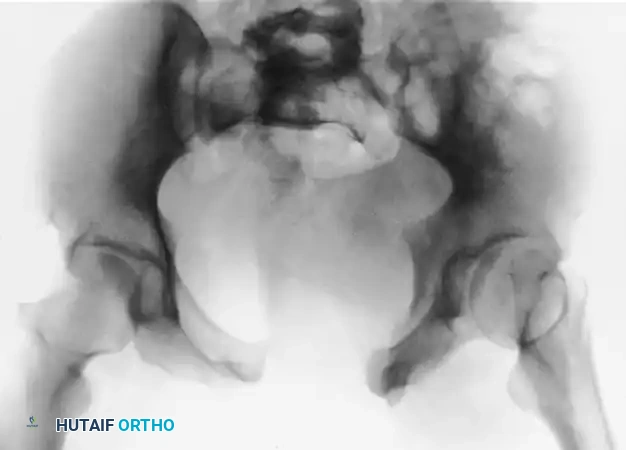

FIGURE 56-46 A-D: Young and Burgess lateral compression type III (LC III) injury with marked displacement of the right pubic ramus. Preoperative anteroposterior, inlet, outlet views, and CT scan demonstrate the severe rotational instability.